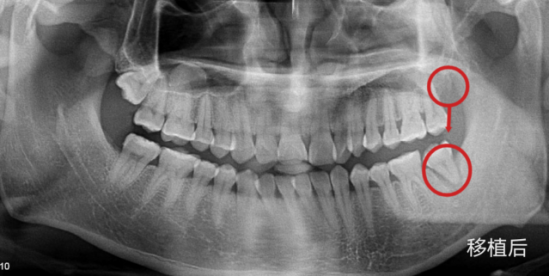

变废为宝!带你了解自体牙移植

自体牙移植,是指利用自己的牙齿(智齿、正畸需要拔除的牙等)来替代因为龋坏、外伤或者肿瘤侵犯而无法保留需要拔除的患牙。临床上最常见的自体牙移植来源是我们的第三磨牙,即智齿。

3.将智齿种在原“坏牙”处;

4.大功告成。

自体牙移植成功率主要体现在三方面:医生技术、患者意识和智齿自身的条件。目前我们开展的智齿移植,随访至今,成功率在95%以上(随着随访时间延长,成功率会降低)。